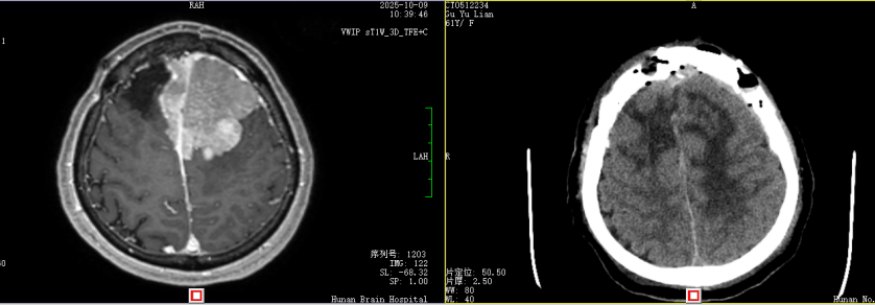

患者术前术后影像对比

准备万全后,谷女士被推入了手术室。在显微镜下,手术团队如同在蛛网般的神经与血管中穿行的“微雕大师”,小心翼翼地分离着肿瘤组织。最终,经过8小时的奋战,团队成功切除了复发的肿瘤,并完好地保护乃至修复了被侵犯的矢状窦——这场高难度的“拆弹”行动,终于“有惊无险”地完成了。